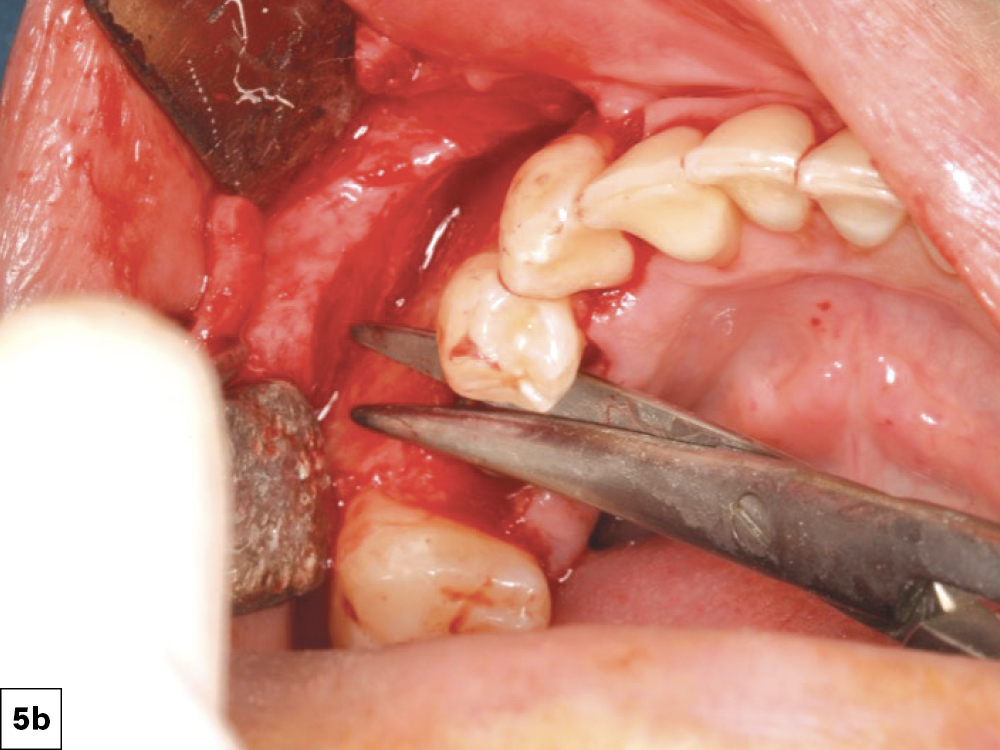

7. Relieving Tissue (Tension-Free)

Excessive flap tension is a leading cause of ILO. This can be prevented by appropriate incision and flap design and periosteal releasing incisions. Clinicians should utilize relieving procedures (i.e., periosteal and blunt dissection) in order to reduce the tension on the incision line. Ideally, the flap should be able to be stretched a minimum of 5 mm past the incision line. Insufficient soft tissue mobility or excessive tension on the tissues during the healing phase may lead to loss of approximation of the tissue margins (Figs. 5a, 5b, 6a, 6b).

Reducing Flap Tension: (a) Periosteal incisions, (b) Blunt dissection with rounded-tipped tissue scissors.

Figures 5a, 5b: Reducing Flap Tension: (a) Periosteal incisions, (b) Blunt dissection with rounded-tipped tissue scissors.